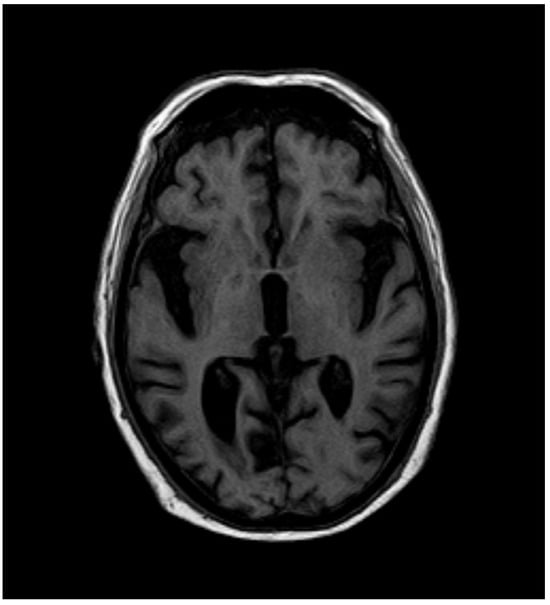

2. Case Report

2.2. Current Disease

2.3. Additional Tests